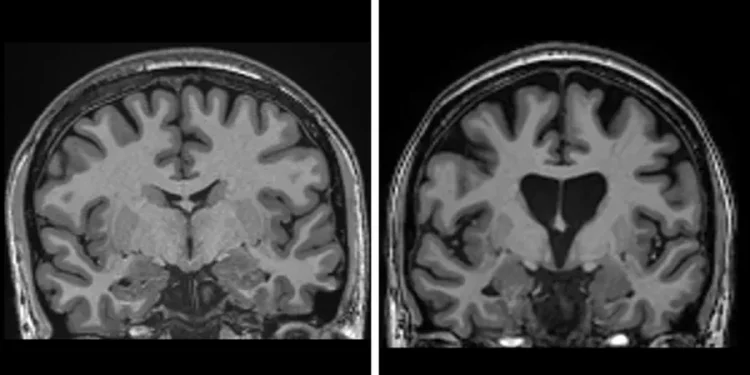

Sëmundja e Huntington është një çrregullim neurodegjenerativ gjenetik që ndikon në koordinimin e muskujve dhe çon në dobësim kognitiv dhe demencë.

Sëmundja e Huntington shkaktohet nga një defekt në një pjesë të ADN-së sonë të quajtur gjeni huntingtin. Ky mutacion e shndërron një proteinë të natyrshme, të nevojshme për trurin, të quajtur gjithashtu huntingtin, në një “vrasës” të neuroneve.